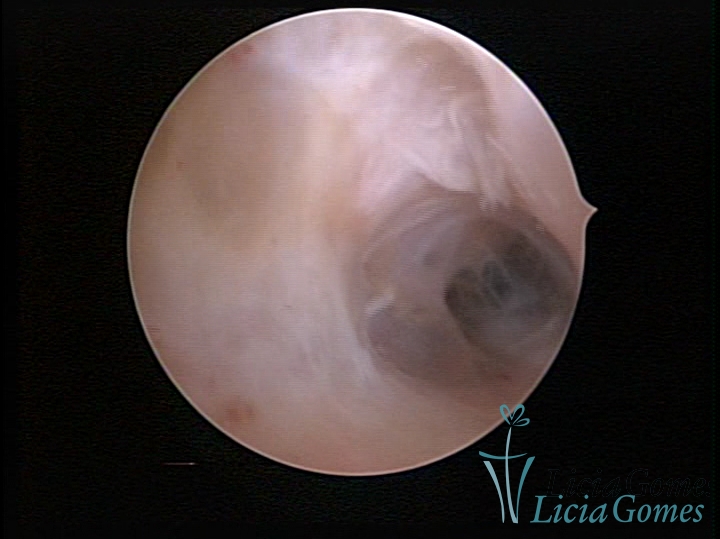

SINÉQUIA TIPO MUCOSA